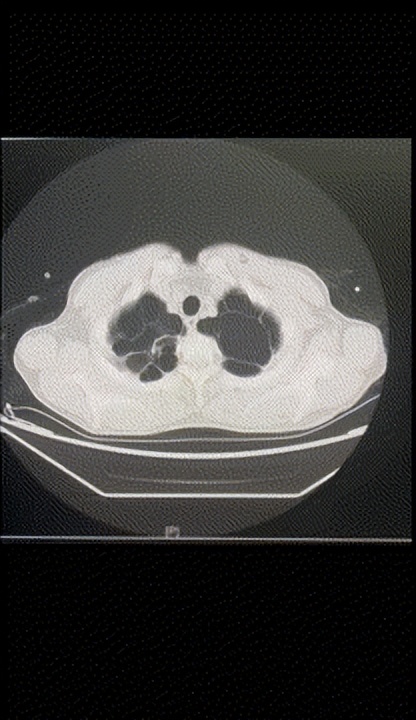

52岁的老刘是一名煤矿工人,几天前他突然晕厥在家中,被紧急送至当地医院,医生考虑为凶险的主动脉夹层。由于病情严重,他随即被转到福建医科大学附属协和医院心外科,医院立即开通绿色通道,通过进一步的检查发现,老刘被确诊为A型主动脉夹层,而且撕裂范围很大,从主动脉根部向下一直撕裂到双侧髂动脉,并且他的右颈总动脉被夹层撕裂导致闭塞,左侧肢体无力。同时,医生惊讶的发现,由于长期的挖煤工作,老刘两侧的肺部空泡化十分严重,肺功能因此严重受损。

▲老刘的肺部空泡化严重